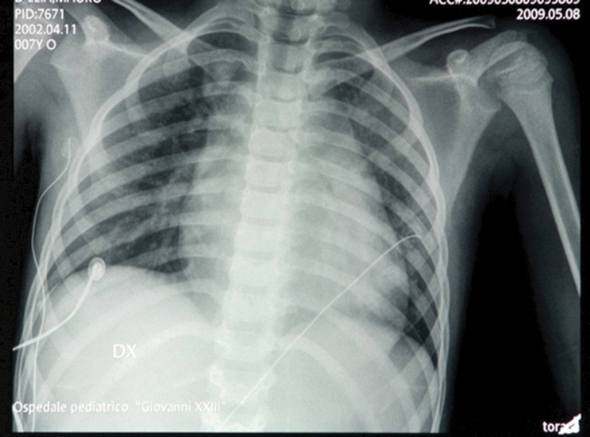

EKG

APLS Case#17 Myocarditis

By Ali Hasan